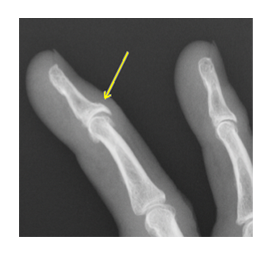

ヘバーデン結節とブシャール結節は、どちらも指の関節に起こる変形性関節症で、ヘバーデン結節は指の第一関節(DIP関節)、ブシャール結節は第二関節(PIP関節)に痛み、腫れ、変形が生じる病気です。

ヘバーデン結節